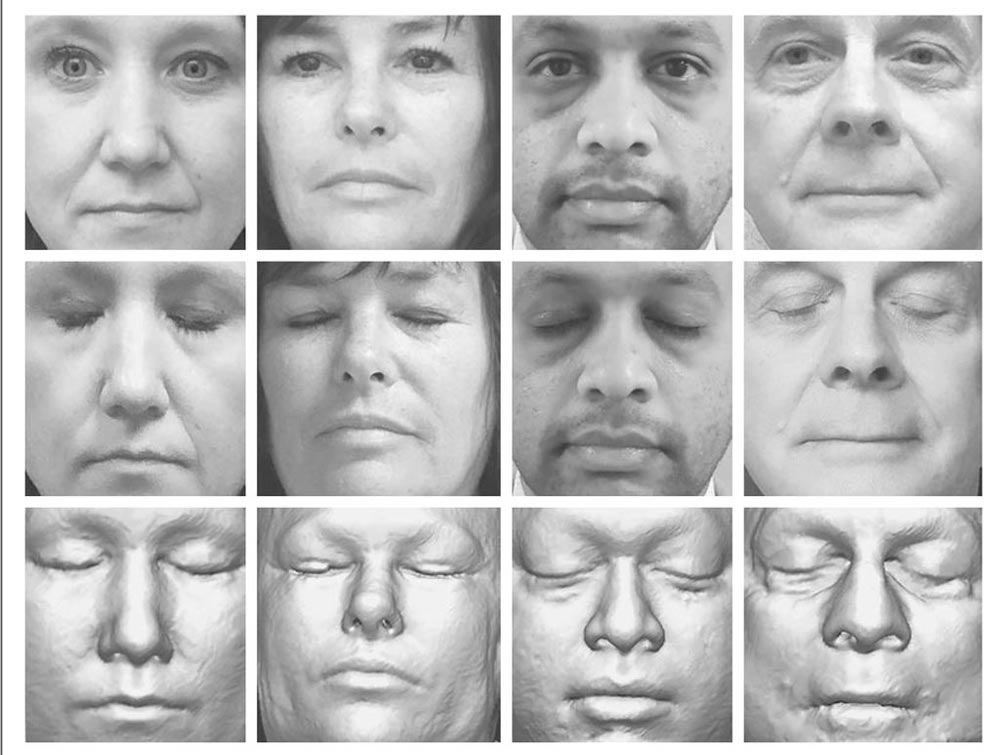

Die Antwortet lautet: Ja. Die Mayo-Klinik rekrutierte 84 Freiwillige zwischen 34 und 89 Jahren, von denen ein aktueller MRT-Scan vorlag. Sie wurden aus fünf verschiedenen Perspektiven fotografiert. Zeitgliech rekonstruierten die Forscher das Gesicht der Person digital anhand des MRT-Scans.

Anschließend gaben sie einer Gesichtserkennungssoftware von Microsoft die Aufgabe, die Fotos der Personen mit den aus den MRT-Scans rekonstruierten Gesichtern zusammenzuführen. Die KI konnte 70 der 84 MRT-Scans korrekt dem Foto zuordnen. Für weitere zehn Personen war der passende MRT-Scan zumindest in der Top-5-Auswahl.

Einschränkend ist zu erwähnen, dass die KI die zu den MRT-Scans passenden Gesichter nur aus 84 Bildern heraussuchen musste und nicht aus einer Datenbank mit Tausenden oder Millionen. Die Studie zeigt dennoch, dass die KI-gestützte Identifizierung einer Person anhand eines MRT-Scans prinzipiell möglich ist. Die Ergebnisse der Studie wurden in der Fachpublikation New England Journal of Medicine veröffentlicht.